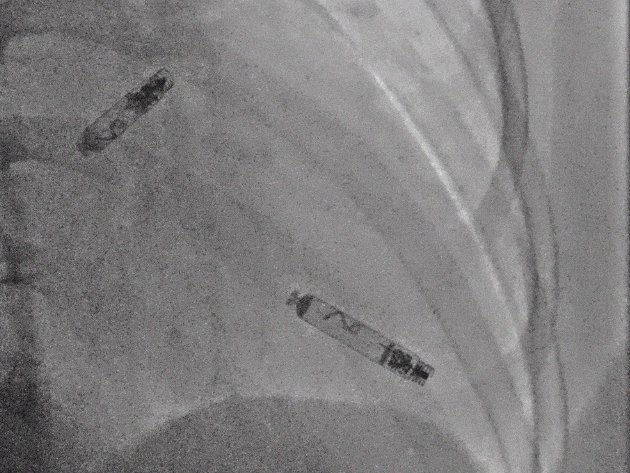

以上两位患者均以标准流程成功植入Aveir™ DR,最终固定位置影像:

病例2 RAO